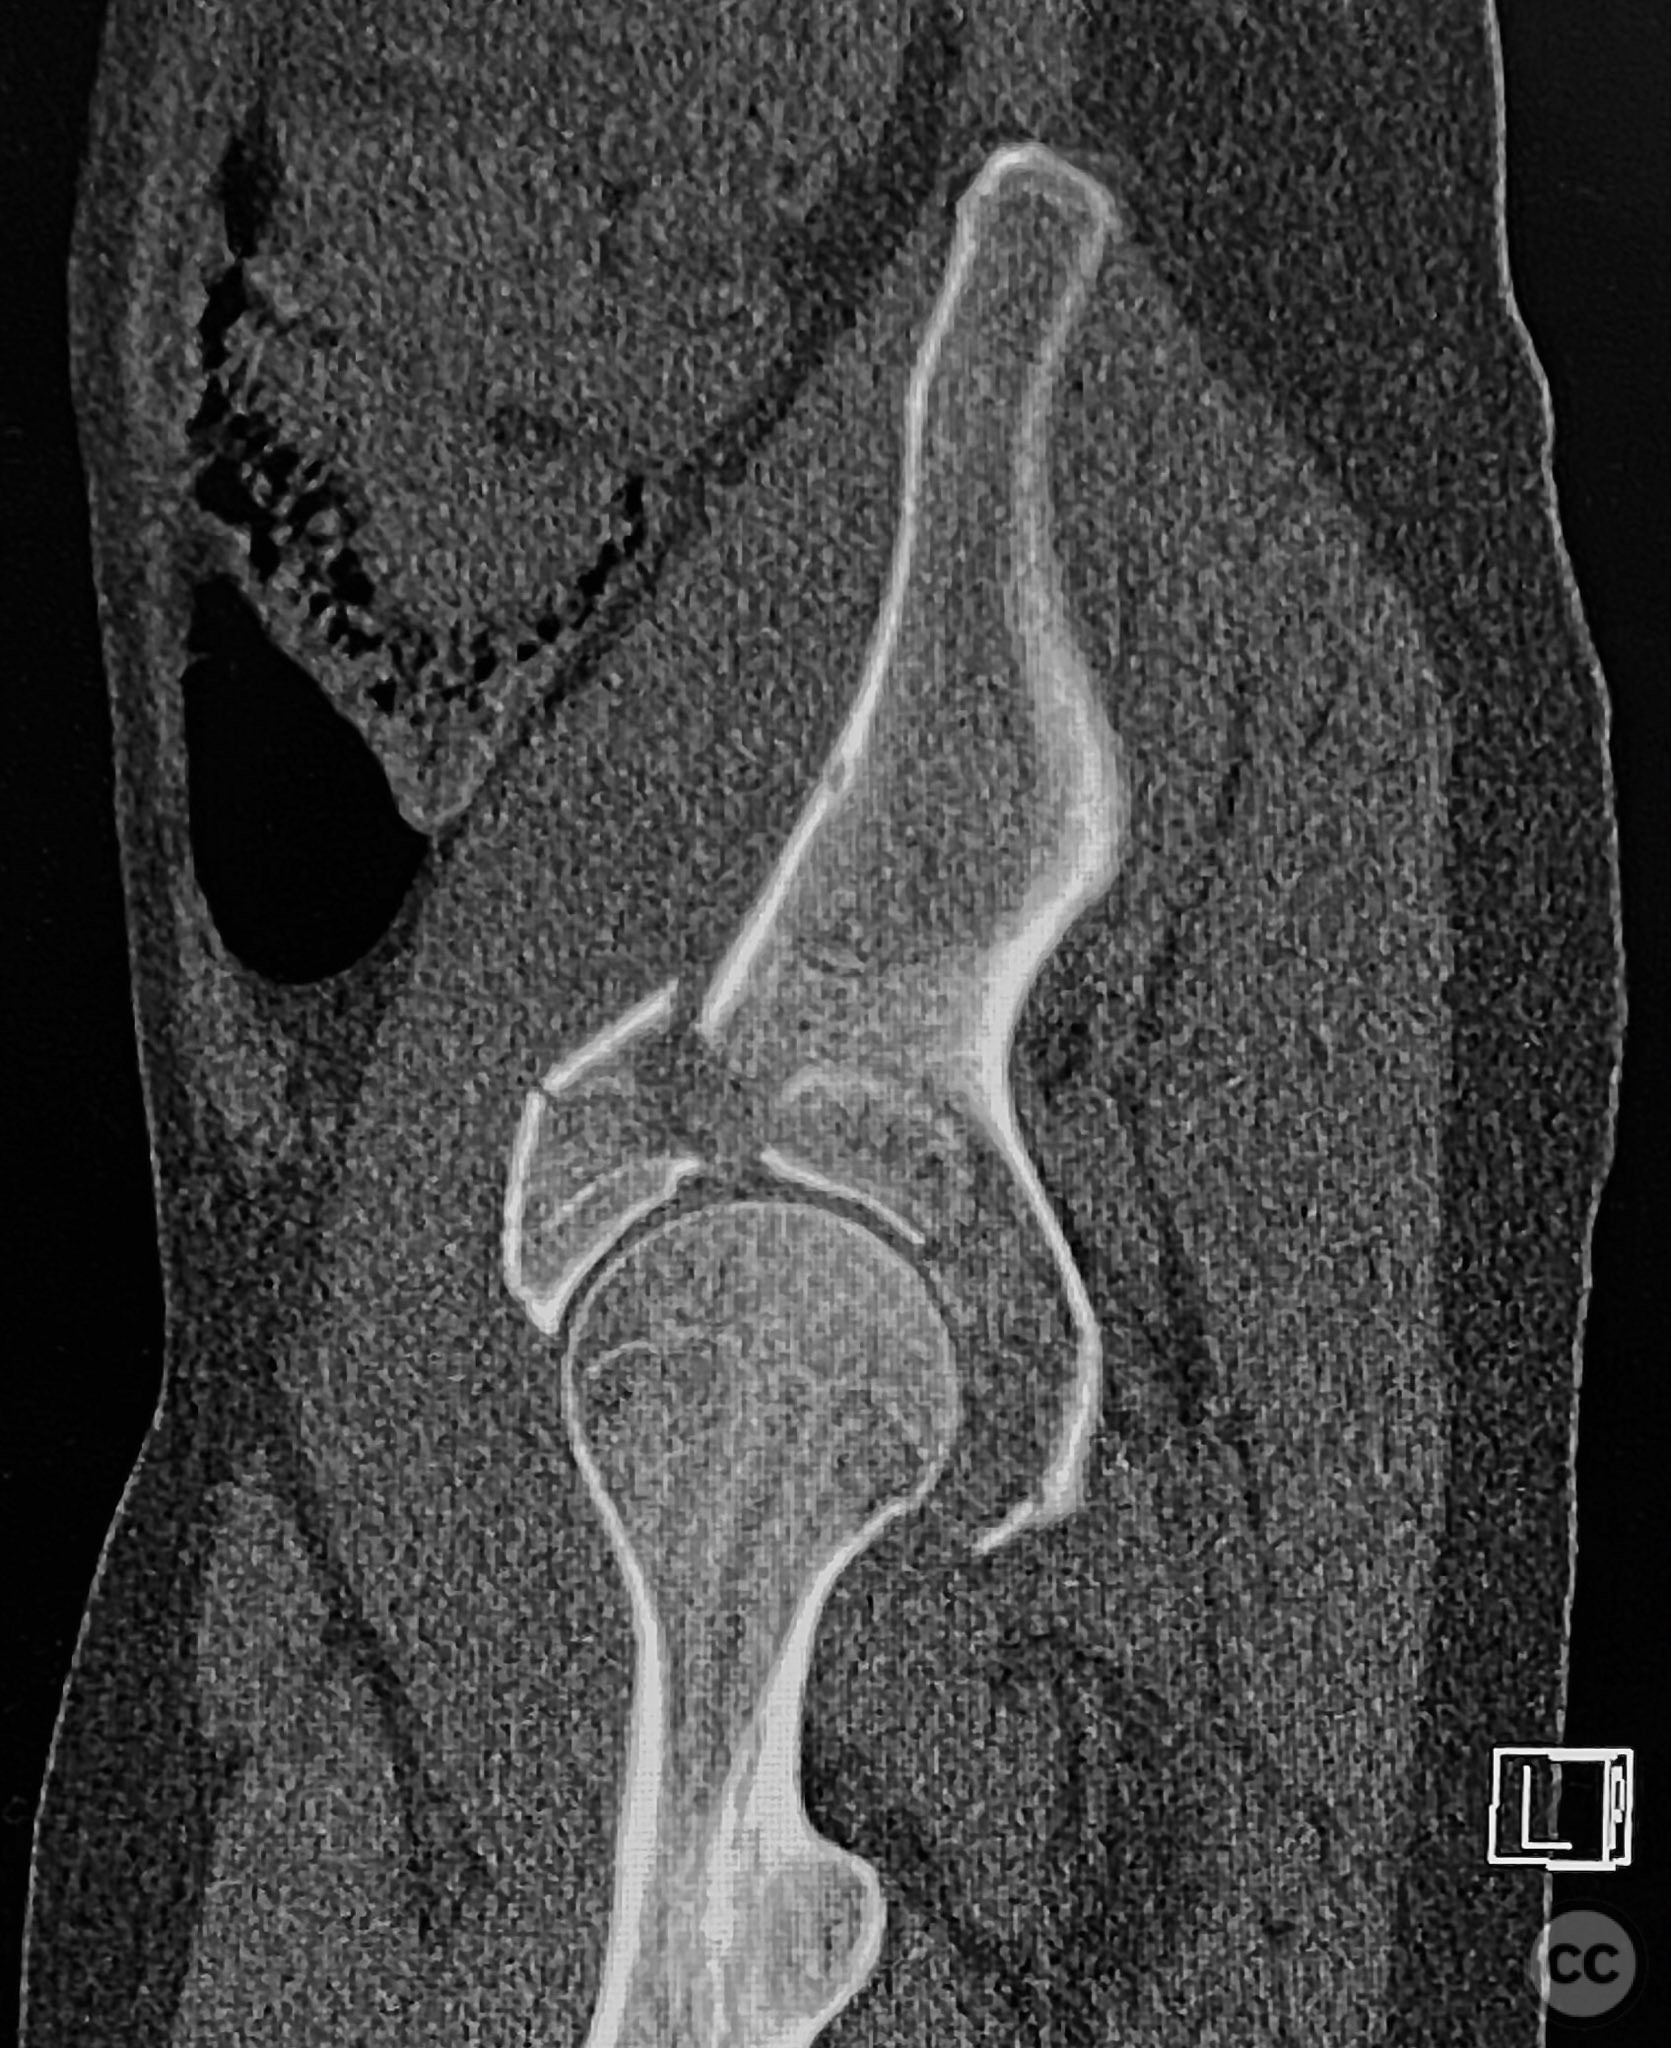

Clinical and radiological findings:  The patient sustained an acetabular fracture with a rare posterior medial dome impaction fragment, as demonstrated on AP pelvic radiographs obtained in skeletal traction. Surface renderings and axial CT images revealed multiple incomplete fracture lines, including a rhomboid-shaped cortical fragment adjacent and proximal to the anterior column/wall fragment. Coronal and sagittal reconstructions further delineated the impacted articular fragment and its relationship to the surrounding acetabular dome. The fracture pattern is classified as AO/OTA 62B3 (associated both-column fracture with dome impaction).

Planning remarks:  The preoperative plan involved an ilioinguinal approach to the acetabulum, utilizing the intrapelvic interval for initial reduction and stabilization of the posterior column with a contoured intrapelvic plate. Sequential reduction of the anterior column and direct management of the impacted dome fragment were planned, facilitated by temporary removal of the rhomboid cortical fragment.